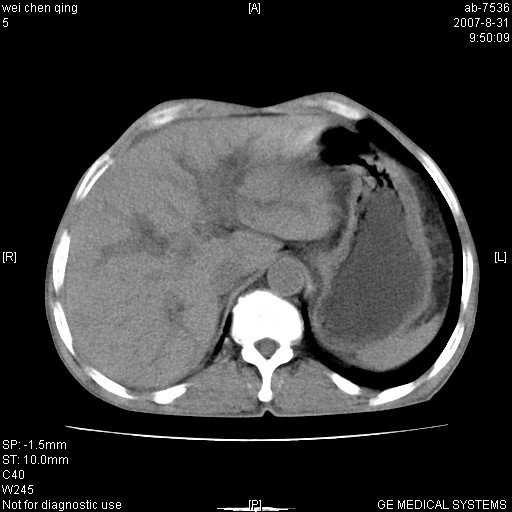

以下是引用zyyzzy在2007-8-31 14:34:00的发言:[br]该病人肝内胆管扩张,胆囊及胆总管未见明显扩张。在倒数第9层图像上可看到左右肝管结合部(肝总管)有软组织影,此处应薄层扫描。考虑肝总管占位(ca)、腹水。[br]